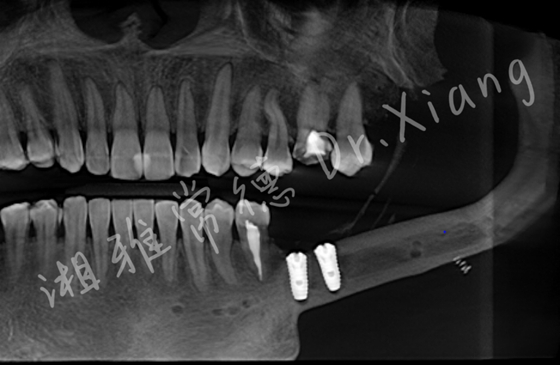

腓骨移植区种植术后影像图

近日,为解决左侧下颌骨缺损所致的咀嚼功能障碍,患者决定接受腓骨移植区种植手术。向峰医师种植团队通过术前多次论证、3D数字化设计及种植体精准匹配,在取出内固定装置的同时,微创植入2枚种植体。手术特邀整形美容烧伤皮肤科唐宁宁医师团队同期参与,切除原有手术瘢痕,并采用美容超减张缝合技术闭合创口,实现功能与美观的双重提升。手术创伤小、恢复快,预计3个月后种植体完成骨结合,患者将恢复左侧咀嚼功能,重返正常饮食。目前,患者已康复出院。